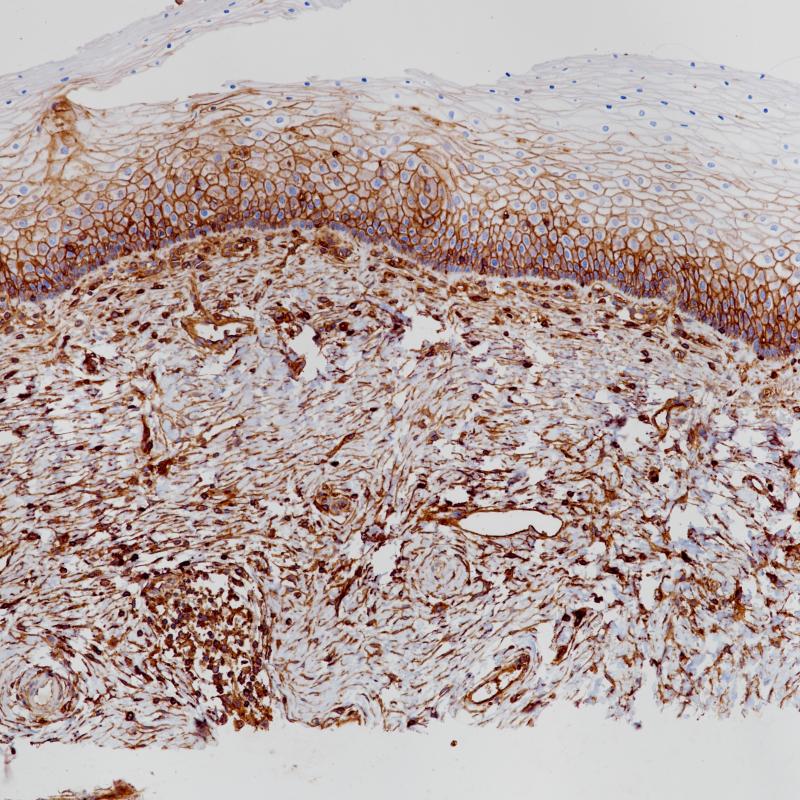

扁桃体MHCⅠ(BP6234)染色

主要组织相容性复合体(MHC)是染色体上由紧密连接的高度多态的基因位点组成的遗传区域。MHC分为Ⅰ类、Ⅱ类和Ⅲ类基因区域。MHCⅠ广泛分布于几乎所有有核细胞的表面,包括正常组织中的脾脏、淋巴结、胸腺淋巴细胞、皮肤、肺、肾、肝和心脏和肿瘤组织。MHC Ⅰ分子分型与器官移植与骨髓移植的匹配,以及多种自身免疫性疾病相关。

亚细胞定位

细胞膜